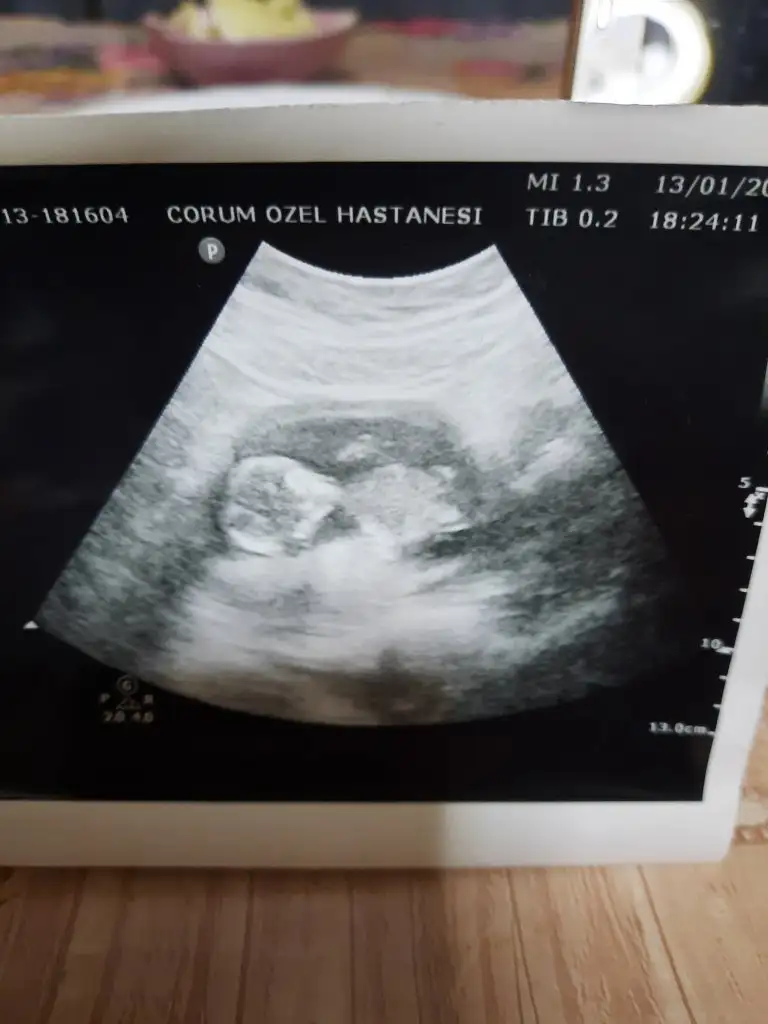

Kız gibi sanki en iyi 11 12 13 haftalar olmalıBuna da bakabilir misiniz yarın yeni kontrolüm var bakalım doktor nediyecek

Teşekkürler 10. Hafta fotoğrafıydı. Yarın 11. Hafta kontrolüm var tekrar atarımKız gibi sanki en iyi 11 12 13 haftalar olmalı

Canım nubu goruluyormu bilmiyorum ama.sizce ne.Kız gibi sanki en iyi 11 12 13 haftalar olmalı

Bana kız gibi geldi. Ama belli olmaz tabi.Canım nubu goruluyormu bilmiyorum ama.sizce ne.

Kiz gibi sankiCanım nubu goruluyormu bilmiyorum ama.sizce ne.

Erkek gibi sanki emin olamadımCinsiyet tahmini alabilir miyim lütfen çok merak ediyorumIkra meyra

Erkek gibi sanki